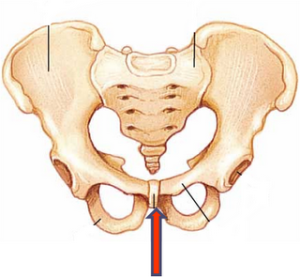

Az alsó osztályok tartozó izmok kialakításában játszik szerepet az urogenitális rendszer és a vastagbelet. Szintén hozzákapcsolt az izom kötegek a gluteus maximus. Továbbá a farkcsont különít fizikai terhelést a medence, mint egy támaszpont. Megdöntéskor ülő személy támasztáspontokként kiállnak ülőgumót és csont (alsó ága).

Elhelyezkedés tailbone a medencében személy